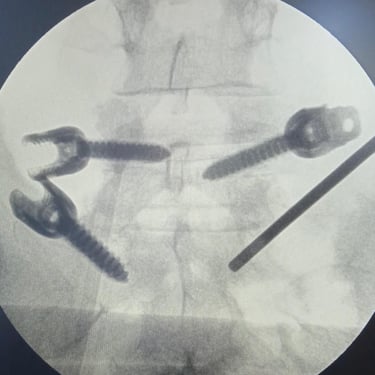

🧠 Listesis L4–L5 con Estenosis Severa: Estabilización con Fijación Transpedicular (FTP) y Fusión Intersomática Transforaminal (TLIF)

La listesis L4–L5 con estenosis severa provoca dolor lumbar e inestabilidad con compresión nerviosa. La fijación transpedicular (FTP) y la fusión intersomática transforaminal (TLIF) permiten descomprimir el canal espinal, estabilizar la columna y mejorar la función de forma segura y progresiva.